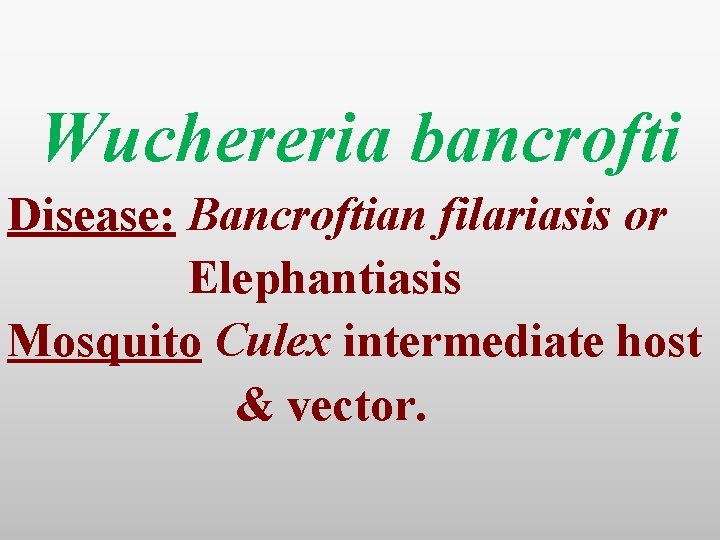

Wuchereria bancrofti Disease: Bancroftian filariasis or Elephantiasis Mosquito Culex intermediate host & vector.